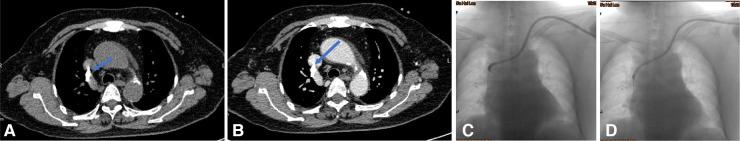

The aim of this study was to evaluate the causes of the dysfunctional tunneled cuffed catheters (TCCs) using multi-spiral computed tomography venography (MSCTV), and to analyze the outcomes of endovascular salvage techniques.

MSCTV showed a range of abnormalities in the hemodialysis (HD) patients, including central venous occlusion ( = 4), fibrin sheath formation ( = 3), malposition of the catheter tips ( = 4), central venous perforation ( = 1), thrombus formation ( = 12), regular catheter exchange without determined lesions ( = 3). Interventional catheter salvage procedures were performed, such as catheter exchange, balloon disruption of a fibrin sheath, angioplasty for central vein stenosis, and stent deployment. The technical success rate for catheter insertions was 100%, and no procedure-related severe complications were observed. The 30-day catheter patency for all assessable catheters was 85.2%.

MSCTV显示血液透析(HD)患者存在一系列异常情况,包括中心静脉闭塞(=4例)、纤维蛋白鞘形成(=3例)、导管尖端位置异常(=4例)、中心静脉穿孔(=1例)、血栓形成(=12例)、无明确病变的常规导管更换(=3例)。实施了介入性导管挽救程序,如导管更换、纤维蛋白鞘球囊破坏、中心静脉狭窄血管成形术和支架置入术。导管插入的技术成功率为100%,未观察到与操作相关的严重并发症。所有可评估导管的30天导管通畅率为85.2%。